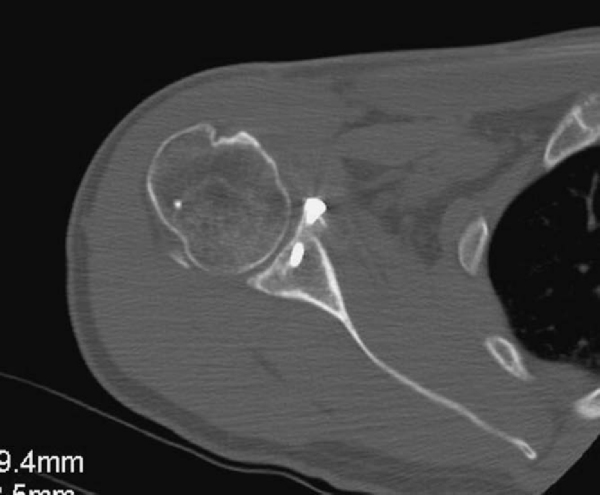

The computed tomographic (CT) scan proves best for assessment of the osseous defect. We have found that plain radiographs will often significantly underestimate the size of the Hill-Sachs or glenoid defect. Multiplanar CT scanning, often with three-dimensional reconstruction, is necessary for the extent of the defect to be truly appreciated. It is essential that CT scans be of high quality and allow accurate preoperative measurements. This allows one to confidently and consistently obtain an appropriately size-matched glenoid or proximal humerus allograft before surgery.

Radiographs are taken at 2, 6, 12, and 24 weeks postoperatively to ensure maintained position of the allograft. If it is clinically warranted, a CT scan can be performed to ensure incorporation of the allograft (

Fig. 14-12

).

Figure 14-12 |